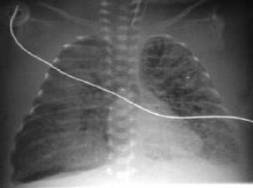

Резкое снижение пневматизации легких, воздушные бронхограммы, границы сердца не различимы, "белые лёгкие" (Рис.7).

Рисунок 7. РДС. Рентгенограмма грудной клетки в прямой проекции, в горизонтальном положении. Интенсивное мелкоточечное затемнение легочных полей - симптом "матового стекла", на фоне которого не дифференцируется тень средостения. Визуализируются линейные просветления, обусловленные заполненными воздухом бронхами - "воздушная бронхограмма". (Диагностика и лечение РДС недоношенных // метод. рекомендация, 2007)